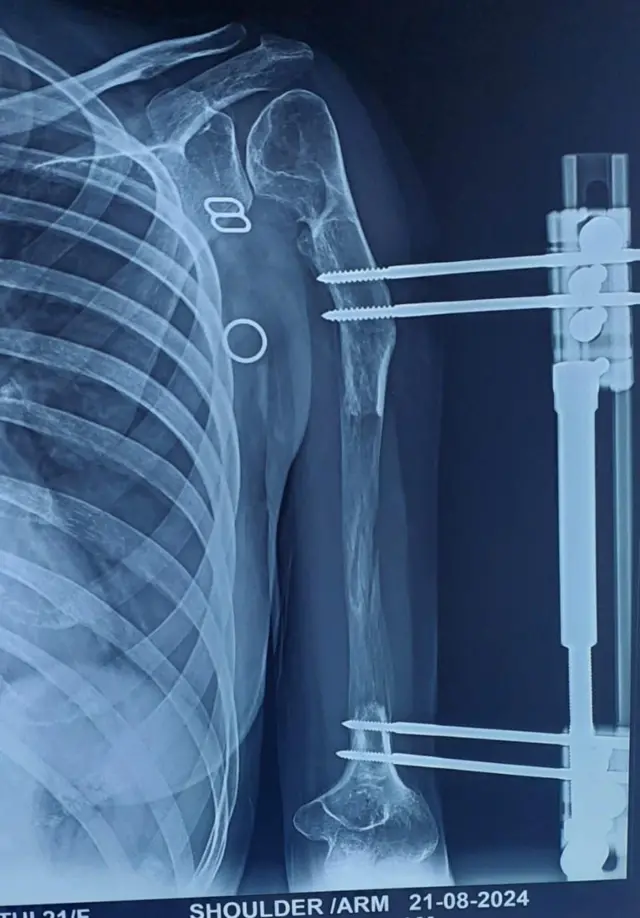

கோமதியின் இடது கை எலும்பை 14 செ.மீ அளவுக்கு வளரச்செய்து, அவருடைய பிரச்னைக்கு தீர்வுகண்டுள்ளனர் திண்டிவனம் அரசு மருத்துவர்கள்.

கோமதிக்கு 14 செ.மீ. வளர்வதற்கு 140 நாட்களாகியுள்ளது. நீட்சியடைந்த சவ்வு, எலும்பாக வலுப்பெற அதைவிட இருமடங்கு நாட்களாகும். அதாவது 280 நாட்கள்.

"இங்த சிகிச்சை முற்றிலும் முடிந்து, கோமதியின் கை இயல்பாக கிட்டத்தட்ட ஓராண்டாகிவிட்டது. 2024, ஜனவரி மாதம் அறுவை சிகிச்சை செய்து, தற்போது அவர் இயல்பு நிலையில் உள்ளார்." என்கிறார் மருத்துவர் சுரேஷ்.

"கோமதியின் பாதிப்புக்குள்ளான கையின் எலும்பு முன்பு 14 செ.மீ. நீளம் தான். இப்போது வளர்ந்துள்ள 14 செ.மீ உடன் சேர்ந்து 28 செ.மீ ஆகி, இயல்பாக காட்சியளிக்கிறது. எலும்பு மட்டுமல்லாமல் அதனுடன் தோல், ரத்தக்குழாய், நரம்பும் நீண்டுள்ளது. திசுக்கள் சேதமடையாமல் அதை நீட்சியடைய வைக்க முடியும் என்பதுதான் இந்த சிகிச்சை முறை. இப்போது கோமதியால் எல்லோரையும் போன்றே ஆரோக்கியமாக எல்லா வேலைகளையும் செய்ய முடியும்."